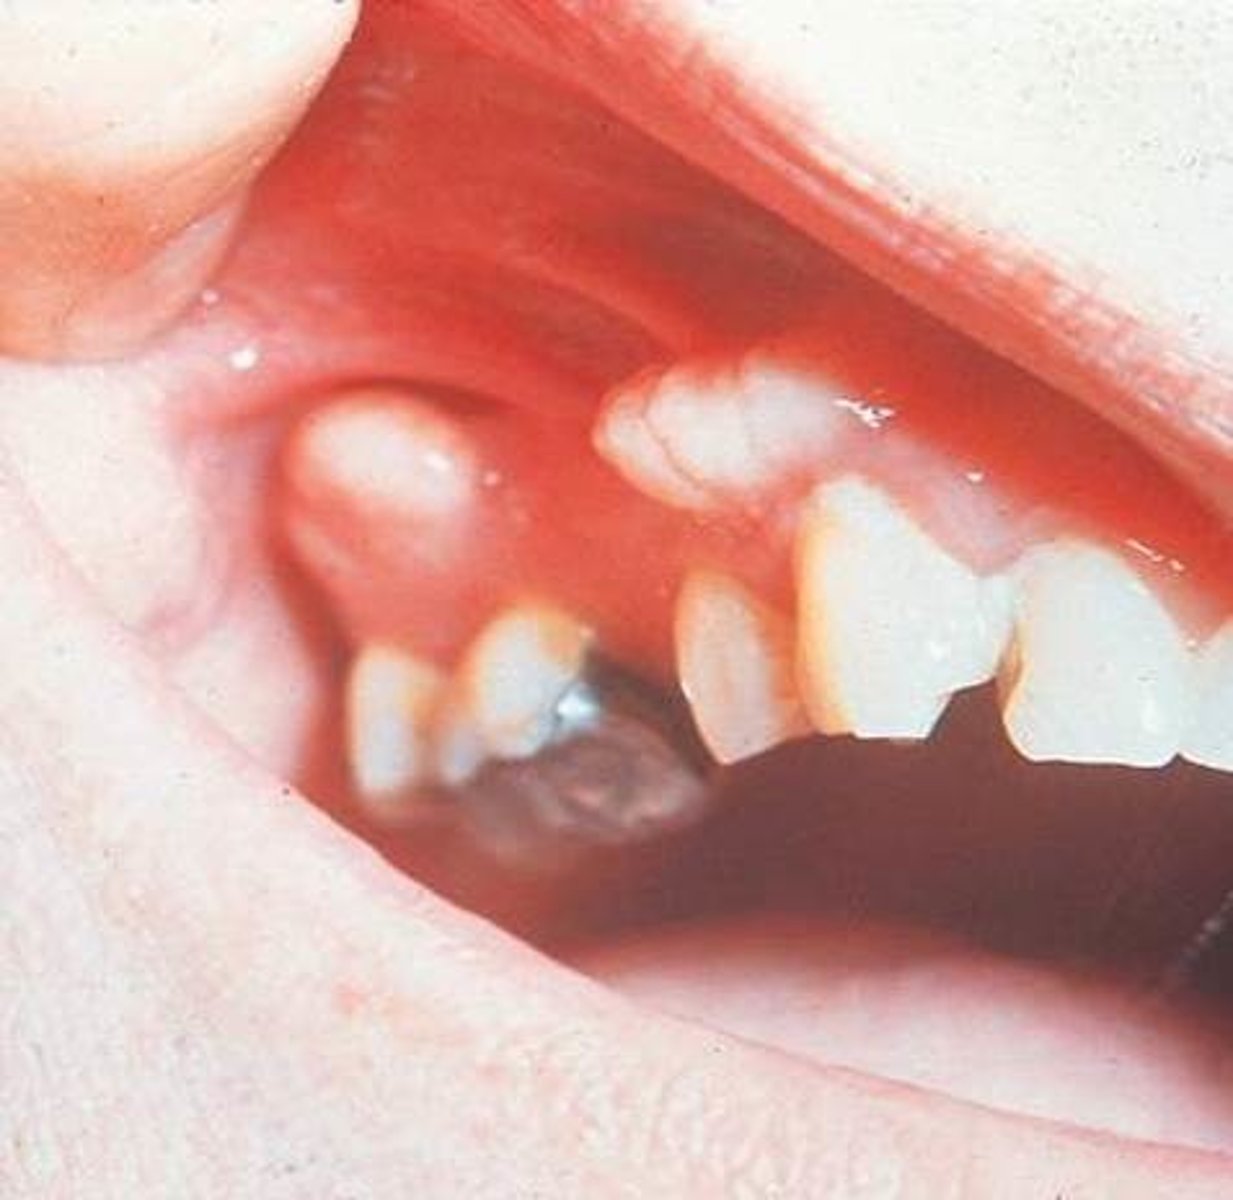

Cherubism

Progressive bilateral facial swelling due to cherubism, first appears when the patient is _____ to _____years of age

1.5 to 4

Radiographs of the Cherubism reveals a characteristic of:

soap bubbles or multilocular appearance